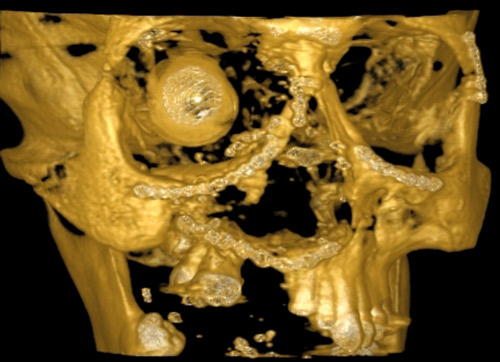

Høyoppløsnings computertomografi av typen «cone beam computer tomography» (CBCT) er en teknikk som er basert på røntgen transmisjonsprojeksjon av bestemte todimensjonale absorpsjoner. Teknikken kalles også digital volumtomografi (DVT) og ble opprinnelig utviklet for diagnostikk innen dental og maxillofacial radiologi. Metoden kan blant annet gi en presis 3D-avbildning av beinete strukturer i ansiktet uten metallartefakter. På grunn av kompakt størrelse av apparatet, enkel teknisk håndtering og rask undersøkelse er digital volumtomografi et godt diagnostisk redskap innen ansiktstraumatologi og i øre-nese-hals-området. Det er omdiskutert hvorvidt denne CT-metoden har høyere eller lavere stråledose sammenliknet med konvensjonell CT. Roberts og medarbeidere målte en stråledose for fulldose skanning av hodet til å være 92,8 µSv til 206,2 µSv og dermed mindre enn for tilsvarende konvensjonelle CT-undersøkelser (1).

Figur 1 viser avbildning med digital volumtomografi av en pasient med skuddskader etter innsetting av en stor mengde osteosyntesemateriale. Denne metoden ga en fremstilling uten artefakter, mens tradisjonell CT hadde begrenset nytteverdi pga. metallartefakter og utilfredsstillende 3D-modellering (fig 2).